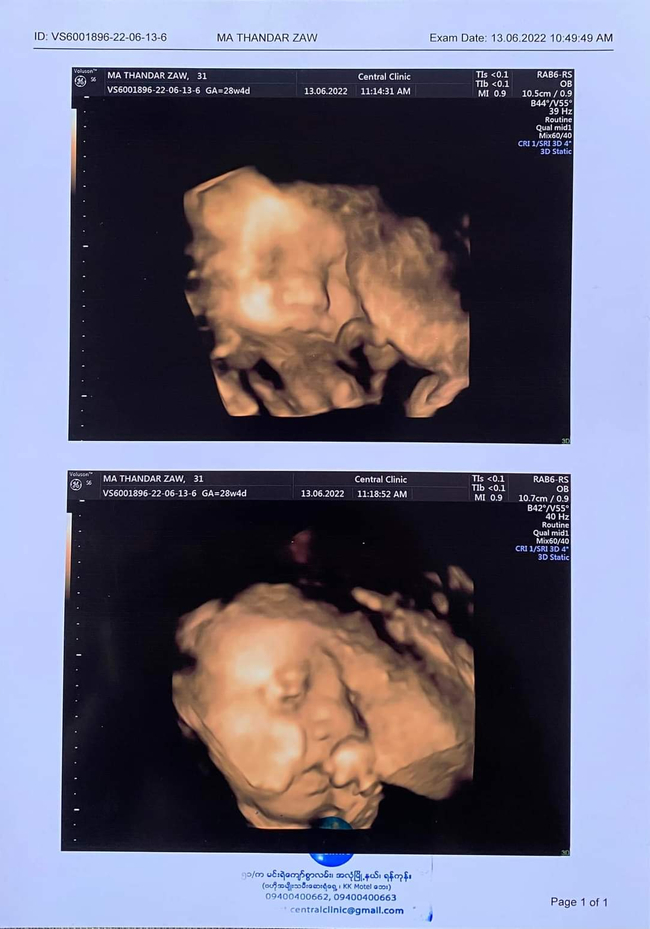

သူမရဲ့ဗိုက်ထဲက သမီးလေးကို အာထရာဆောင်းရိုက်ခဲ့ပြီး ဒီပုံလေးတွေကို Facebookပေါ်ဝေမျှခဲ့ပါတယ်။

သူမရဲ့ ဗိုက်ထဲက အခုတည်းက သူ့အဖေသားဂန်းအကျင့်စရိုက်တွေတူနေပြီဆိုတာကိုလည်း အခုလိုရေးသားခဲ့ပါသေးတယ်

"အမေရဲ့အချင်းနားကကိုမျက်နှာမခွာတာ?

သူ့မျက်နှာလေးအပြည့်ကို 4Dရိုက်မရဘူး??

သူအဖေအတိုင်းပဲကင်မရာမကြိုက်သောလေး?

အဖေနဲ့တူချင်ရင် ပါးချိုင့်လေးရယ် အသံလေးရယ်တူနော်သမီး?"